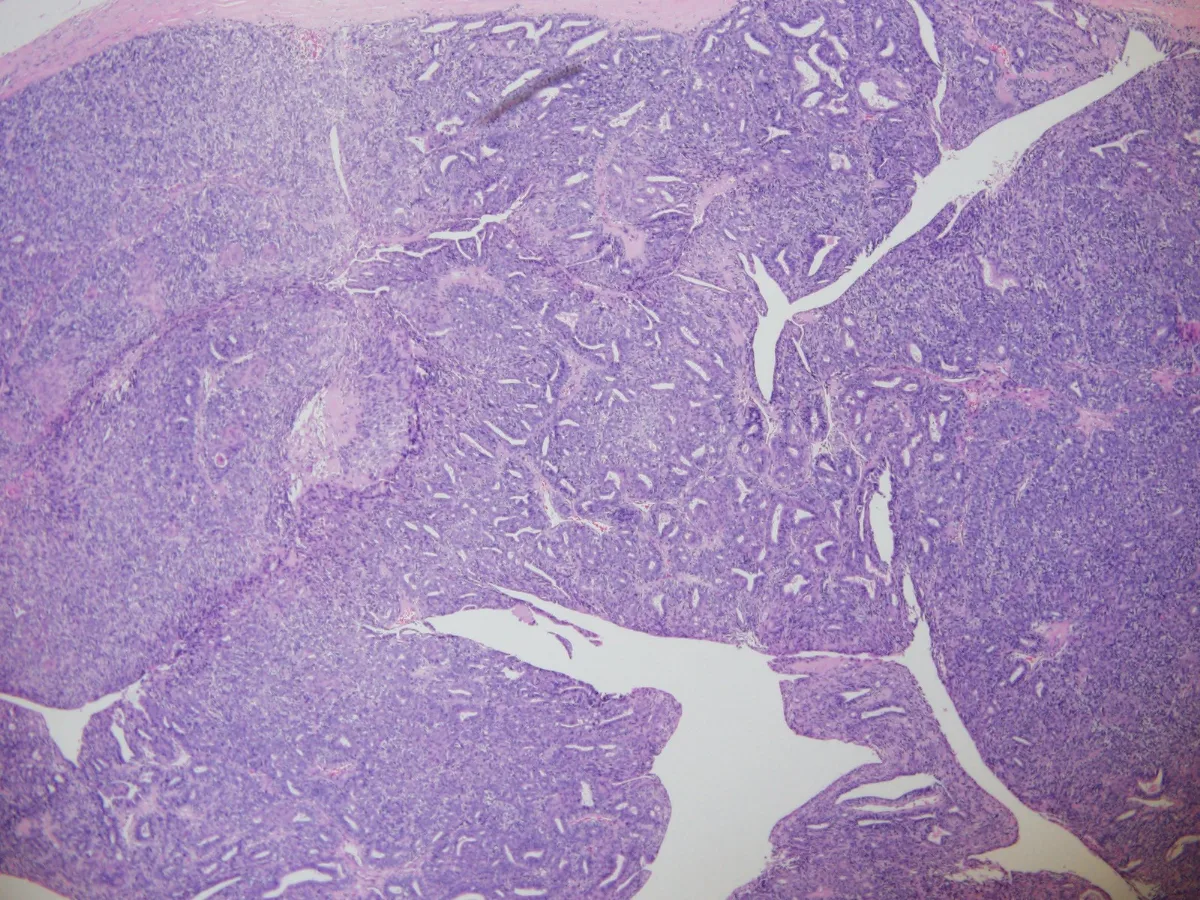

1- Panoramica

- Histológicamente, el APD es un tumor multinodular, bien circunscrito, que presenta patrones de crecimiento sólido, quístico y papilar. (PMID: 32002453)

- La característica típica son glándulas fusionadas o papilas verdaderas, constituidas por células epiteliales cúbicas o columnares, que ocasionalmente muestran secreción apocrina, con zonas revestidas por una capa periférica de células mioepiteliales. (PMID: 23026931)

- El grado de atipia citológica, el índice mitótico y la presencia de necrosis es variable entre casos. (PMID: 23026931)